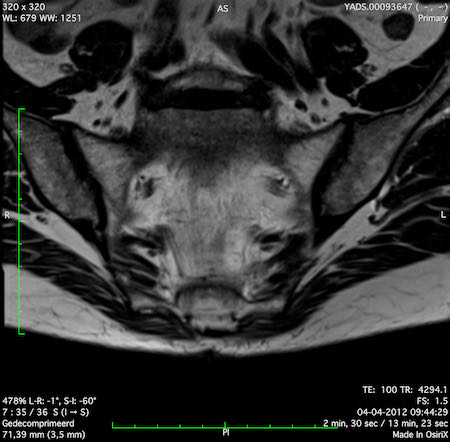

Hình ảnh

Các hình ảnh được cung cấp cho thấy ung thư biểu mô tế bào nhẫn với tình trạng dày lan tỏa thành trực tràng, hình ảnh bia bắn điển hình, và sự xâm lấn mỡ mạc treo trực tràng.